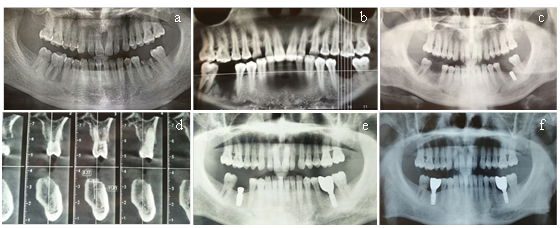

General population: A 56-year-old male patient settled in the plateau area complained pain of his mandibular first molar (Health status: none smoking, fasting blood glucose: 7.8mmol/L).The two mandibular first molars were removed due to vertical root fracture and residual root (Figure 2a). Four months later, the alveolar fossa of 36-tooth was well healed. However, the 46-tooth’s alveolar fossa was healed poorly (Figure 2b).

Surgical plan: The site of left mandibular first molar was implanted with Megagen implant (4.5*10mm). Moreover, the site of right mandibular first molar was placed bone scraps and bone substitutes (Bio-Oss®) and been covered with a resorbable collagen membrane (Bio-Gide®) above. Double-layer membrane technique was applied. Panoramic radiograph showed expected result after operation (Figure 2c). After six months, the result showed that the alveolar fossa of right mandibular first molar had a good osteogenic effect (Figure 2d). The left mandibular first molar’s abutment was repaired with an all-ceramic crown and the site of right mandibular first molar was implanted with Megagen implant (4.5*08mm) (Figure 2e). After three months, the right mandibular first molar’s abutment was repaired with an all-ceramic crown. The patient was reviewed every three months in the first year, and every six months thereafter (Figure 2f).

Figure 2(a) Panoramic radiograph before extraction. (b) Four months later after extraction. (c) Panoramic radiograph after GBR. (d) Six months later after GBR. (e) Panoramic radiograph showed a considerable osteogenic effect around dental implant. (f) Stableosteogenic effect after two years.